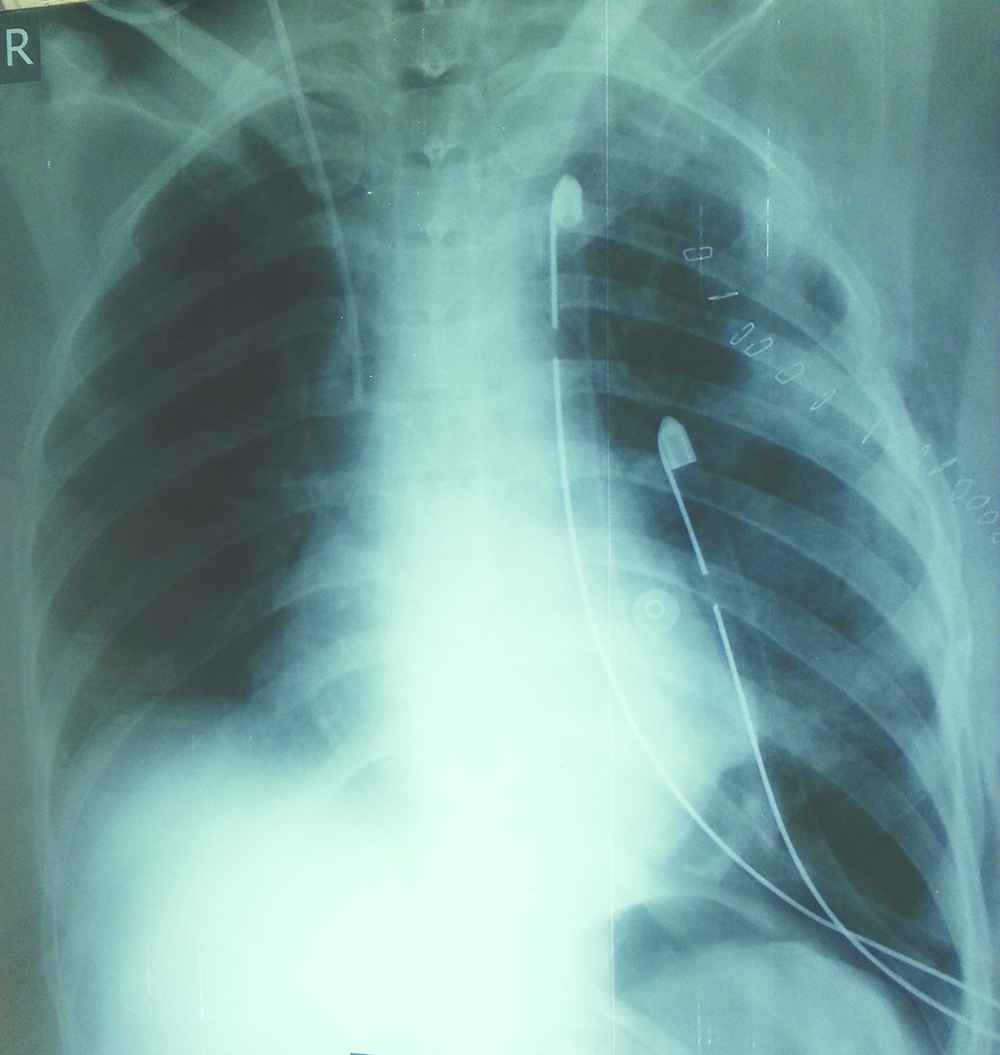

The chest X-ray scan showed a homogenous opacity occupying the left hemithorax pushing the trachea and meditational structure to the right Figure 1. Chest computed tomography (CT) revealed a large heterogeneous mass occupying the left thoracic cavity Figure 2a, displacing the surrounding meditational structures and the trachea to the right, and pushing the diaphragm down Figure 2b, and a collapsed left lung.

On admission chest X-ray (CXR) showing homogenous opacity occupying left hemithorax with tracheal and mediastinal right shifting (arrows).